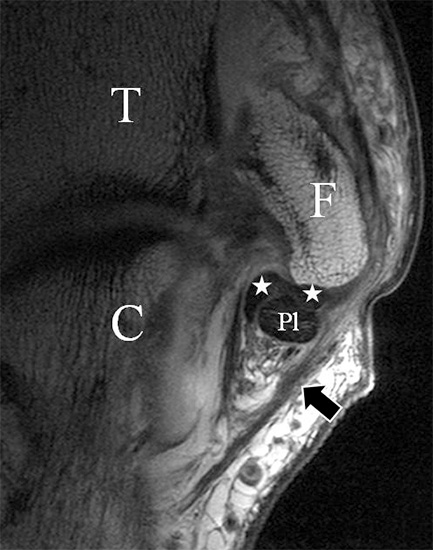

Man unterscheidet bei dem Ligamentum deltoideum eine tiefe Schicht (Pars tibiotalare posterior, Pars tibiotalare anterius) und eine oberflächliche Schicht (Pars tibionaviculare, Pars tibiocalcaneare, Pars tibiotalare posterius superficialis und Tibiospring-Ligament) 10. Hochauflösende Techniken lassen eine differenzierte Beurteilung aller Bandanteile zu. Sowohl rein ligamentäre als auch osteo-ligamentäre Ausrisse sind normalerweise gut zu erkennen. Die Pars tibiotalaris posterior ist multifaszikulär aufgebaut und sowohl axial als auch coronar (Abb. 19 a) gut bildgebend abzugrenzen. Die deutlich kleinere, nur inkonstant angelegte Pars tibiotalare anterior inseriert an einem kleinen Talustuberkel (Abb. 19 b). Ossäre Bandausrisse kommen hier gehäuft vor. Proximal verlaufen die Pars tibiocalcaneare und die Pars tibionaviculare gemeinsam (Abb. 19 c) nach kaudal und trennen sich dann in zum Calcaneus und zum Os naviculare ziehende Bündel auf. Ein besonderer Typ ligamentärer Verbindungen stellt das Tibiospring-Ligament dar. Es verbindet nicht wie für Ligamente typisch zwei Knochen miteinander, sondern es hat seinen ossären Ursprung an der Tibia und inseriert am Pfannenband (Ligamentum calcaneonaviculare plantare, im englischen Schrifttum Spring-Ligament genannt), also nicht ossär. Das Innenband ist mit 60% der Verletzungen am häufigsten betroffen. Isolierte Innenbandverletzungen sind jedoch selten. Sie treten gehäuft assoziiert mit Syndesmosenläsionen, Fibulafrakturen, Verletzungen des Muskulus tibialis posterior und des Pfannenbandes auf (H.-K. Beyer 2003). Entsprechend sollte auf diese Kollateralverletzungen bei der Beurteilung geachtet werden. Eine weitere Folge von Verletzungen des Ligamentum deltoideum ist die chronische Sprunggelenksinstabilität. Arthroskopisch weisen hier bis zu 40% der Patienten einen elongierten Verlauf des Ligamentum deltoideum auf. In diesem Patientenkollektiv besteht auch eine erhöhte chondrale Komorbidität mit arthroskopisch erkennbaren Knorpelschäden (98%) im Gegensatz zu der Patientengruppe (66% Knorpelschäden) mit reiner Außenbandinstabilität 11. Dies belegt die klinische Bedeutung von Innenbandverletzungen.